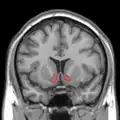

Nucleus accumbens of the mouse brain